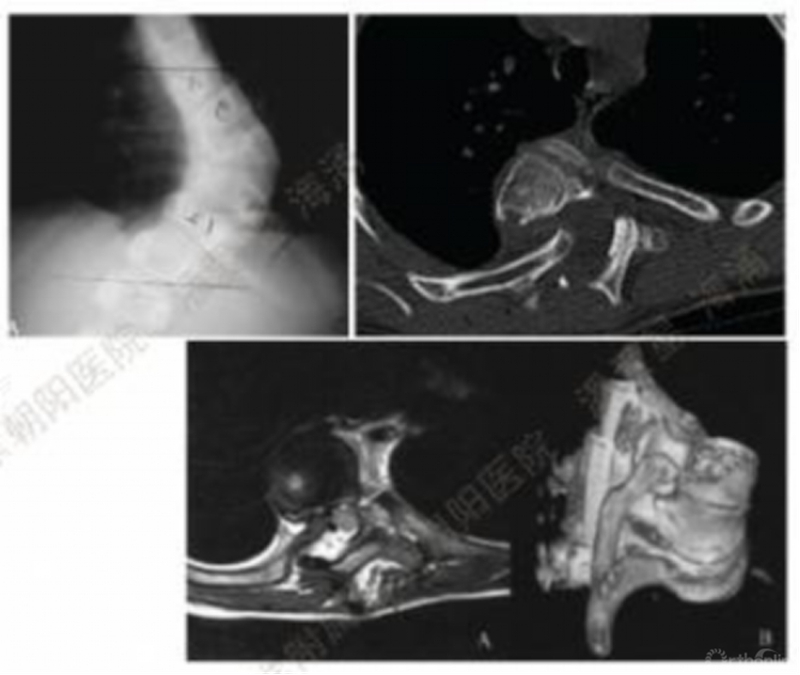

(三)基于核磁的脊髓形态分型

2020年,Lenke教授团队基于脊柱核磁共振中脊髓形态、脑脊液表现及脊髓与顶椎凹侧椎弓根的位置关系,提出了一套脊柱畸形的核磁分型及风险评估系统模型。该系统基于术前脊柱核磁影像学表现评估术中发生脊髓电生理监测信号异常事件的风险。本研究共纳入了128例接受了椎弓根钉棒系统矫形的胸椎畸形患者病例系列。128例患者中,有22例(17%)在术中出现了MEP或SSEP信号丢失。最终21例患者在手术过程中信号逐渐恢复,1例出现新发的神经功能损伤,这例患者神经功能在随访中逐渐恢复,无永久神经并发症。

1型脊髓:髓外观形态呈光滑的圆形或椭圆形,在脊髓和顶端凹椎弓根和/或椎体之间可见脑脊液(CSF);

2型脊髓:脊髓外观形态呈光滑的圆形或椭圆形,在脊髓和顶端凹椎弓根和/或椎体之间未见脑脊液(CSF);

3型脊髓:脊髓外观形态在顶椎凹椎弓根处受压变形/变平,在脊髓和顶端凹椎弓根和/或椎体之间未见脑脊液(CSF)。

文章共纳入了128例胸段脊柱畸形患者,105例患者(82%)接受了后路截骨矫形手术,其中23人(18%)接受了VCR截骨。1型81例(63%),异常监测6例(7%);2型32例(25%),异常监测4例(12.5%);3型15例(11.7%),异常监测12例(80%)。3型脊髓患者的平均年龄较年轻,且畸形程度及畸形角度比例较1型及2型相比明显更为严重

在回归分析中的结果:

1型脊髓是脊髓电生理监测信号异常事件的保护因素(OR=0.17,P=0.0003)。2型脊髓与电生理监测信号异常的发生件没有关联(OR=0.66,P=0.49)。3型脊髓是脊髓电生理监测信号异常事件的危险因素(OR=28.3,P<0.0001)。

评估矫形术中发生神经监测异常事件风险的一种有效的分类模型。可用于指导手术医师指定手术计划及进行术前患者沟通。3型脊髓在畸形矫正过程中监测数据丢失的可能性相对较高,术前做好进行顶椎凹椎弓根切除术或VCR的准备。出现神经监测异常时避免过度地矫形。